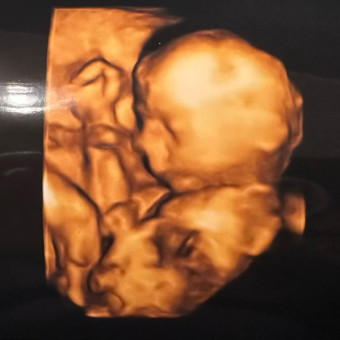

Ashley and Josh’s Baby Registry

July 4, 2026